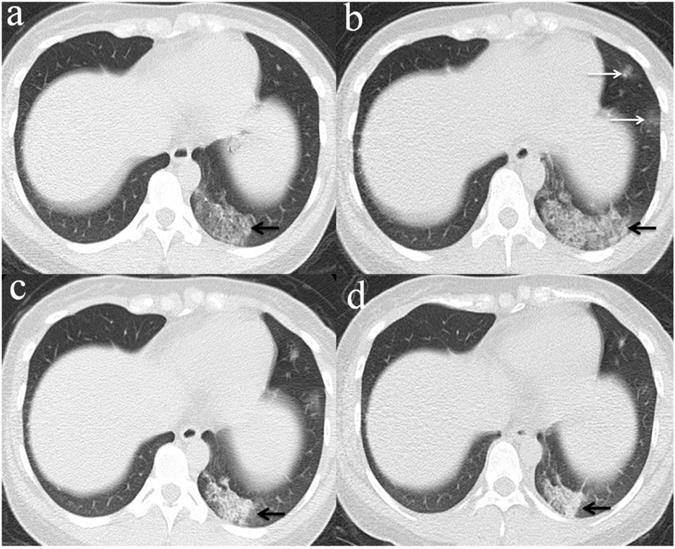

Figure 3

Chest CT imaging findings of COVID-19 pneumonia in a 56-year-old female patient presenting with fever (range:38.1-39℃) for five days. (a) GGO was presented in the upper lobes of bilateral lung with initial negative RT-PCR (arrow); (b) 6 days later, the upper lobes of bilateral lung show extensive consolidation and GGO while RT-PCR test turned positive. (arrow).

Among the 32 patients with negative initial RT-PCR and first positive CT, only 25 patients had the second chest CT when RT-PCR test turned positive. GGO was the most frequent CT findings at the first and second chest CT [96.9% (31/32) and 84% (21/25), respectively] (Figure 3), and the right upper lobe (22/32[68.8%]) was the most commonly affected at initial chest CT scan with negative RT-PCR. Consolidation was more frequently observed on the lower lobes, and more frequently detected during the second CT (16/25[64.0%]) with positive RT-PCR than the first CT with initial negative RT-PCR (17/32[53.1%]) (Table 2, Figure 3, 4). More than two affected lung lobes were detected in 65.6% (21/32) patients at the first chest CT, and this ratio went up to 84.0% (21/25) at the second chest CT, while 12/25 (48.0%) patients had all five lobes affected. Bilateral lung involvement was more often than unilateral both at the first (22/32[68.8%]) and second (22/25[88.0%]) chest CT (Table 2). Subpleural distribution characterized the lung involvement in most patients (24/32[75.0%]) at the first chest CT, which presented in 11/25 (44%) patients at the second CT (Figure 5). However, the crazy-paving pattern is not as common at the first (4/32[12.5%]) and second (3/25[12.0%]) chest CT. No patients had cavitation, calcification, or lymphadenopathy.